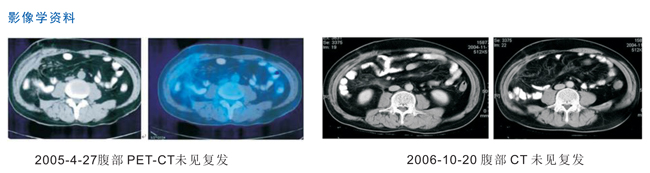

病人,男,62歲,因右下腹脹痛4月,加重1周于2004年4月份在當(dāng)?shù)匾浴瓣@尾炎”剖腹探查發(fā)現(xiàn)右回盲部結(jié)腸腫物約7cm×8cm大小,手術(shù)切除后病理為高分化腺癌,術(shù)后未行放化療,2004年9月至2004年11月行NK細(xì)胞回輸6次,現(xiàn)患者一般情況可,無(wú)腹痛腹脹。

女,69歲,左乳腺癌術(shù)后患者?;颊咭蜃笕橄倌[物3年于2004-7-29行左乳癌改良根治術(shù),用環(huán)磷酰胺+阿霉素+5-氟脲嘧啶方案化療2程,2004-10-22至2004-12-17行NK細(xì)胞回輸6次,2005年4月-9月行CIK細(xì)胞回輸6次,2006-11-20 胸部PET-CT示未見復(fù)發(fā)。